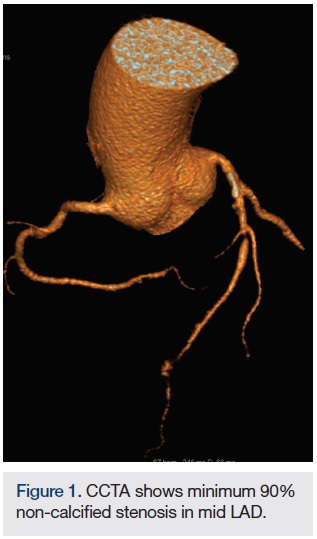

The SOMATOM Force CT system (Siemens Healthcare), which enables fast temporal resolution, was used to perform a coronary CT angiogram (CCTA) on an emergency department patient. The CCTA displayed a 90 percent or greater non-calcified short stenosis in the mid left anterior descending coronary artery (LAD). The next day, the patient’s coronary catheterization revealed a mid-LAD stenosis, type B1 and ulcerative, just distal to a moderate-sized diagonal. A drug-eluting stent was placed; no residual stenosis and normal distal flow was observed. A day after stent placement, the patient was discharged.

Images/courtesy St. Elizabeth Hospital, Edgewood, Kentucky